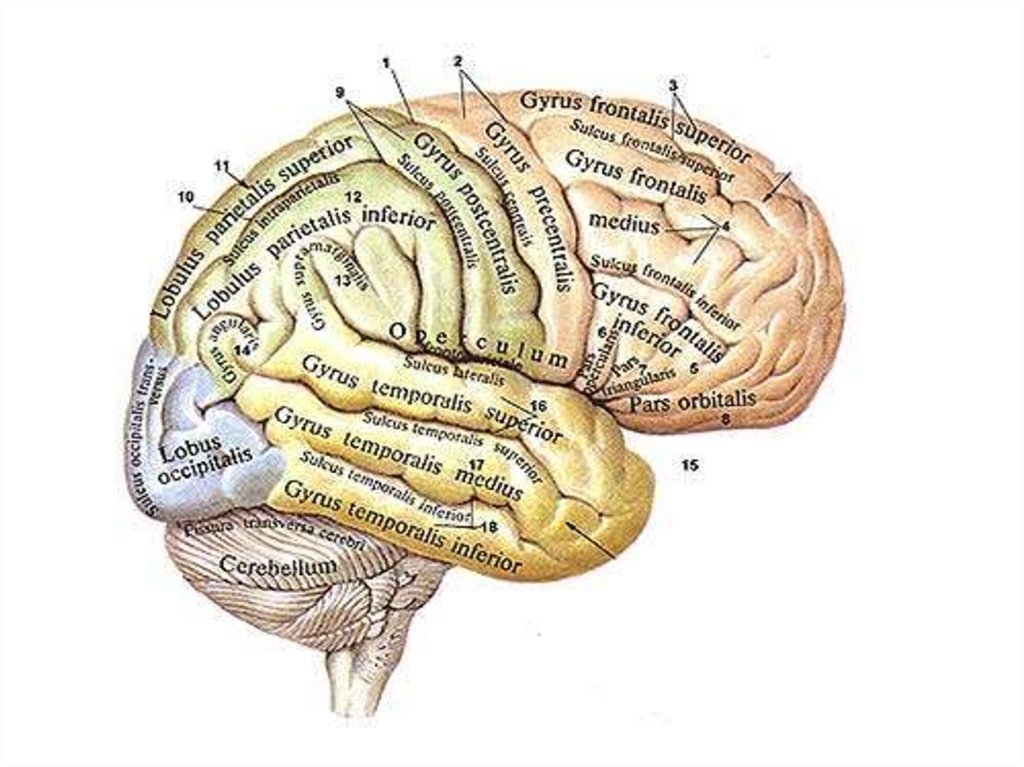

Супрамаргинальная извилина: Функции и Исследования